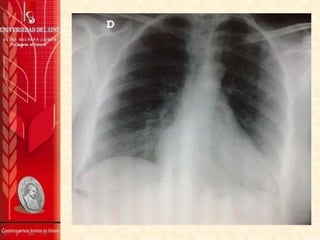

• Hemograma, Bun, Creatinina, Glicemia, TP, TPT,

ionograma, electrocardiograma, CK total, CK

MB, Troponina I, RX de tórax